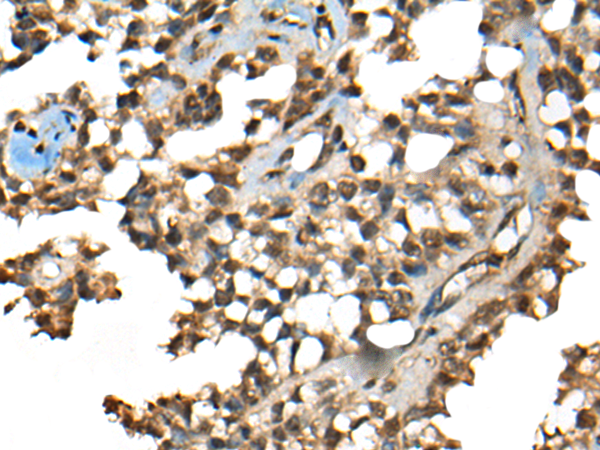

IHC positive control: |

Human esophagus cancer and human ovarian cancer |

IHC Recommend dilution: |

50-300 |